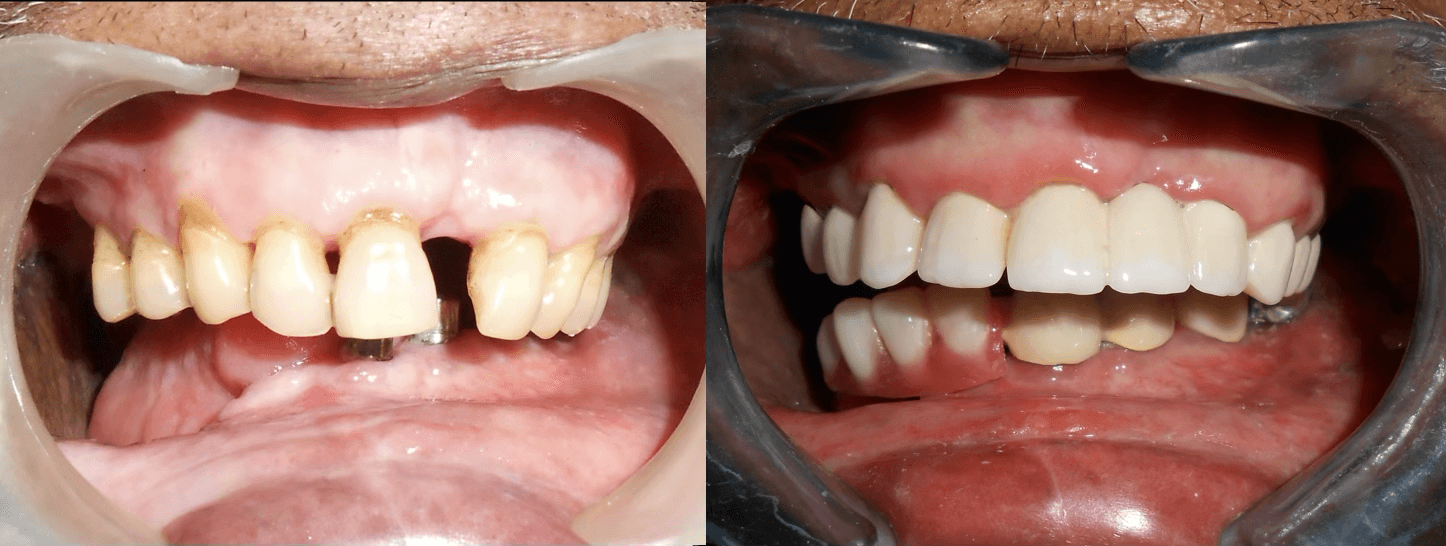

Initial condition

Final result

A 72-year-old male oral cancer survivor visited our dental center after surgical removal of the right side of his mandible. Patient had multiple missing and attrited teeth with significant functional impairment. Treatment involved implant-supported lower teeth with PFM crowns and precision-attached removable denture for hemimandibulectomy rehabilitation.